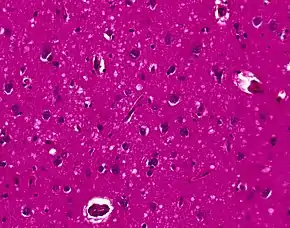

The classic histologic appearance is spongiform change in the gray matter: the presence of many round vacuoles from one to 50 micrometers in the neuropil, in all six cortical layers in the cerebral cortex or with diffuse involvement of the cerebellar molecular layer.[48] These vacuoles appear glassy or eosinophilic and may coalesce. Neuronal loss and gliosis are also seen.[49] Plaques of amyloid-like material can be seen in the neocortex in some cases of CJD.

However, extra-neuronal vacuolization can also be seen in other disease states. Diffuse cortical vacuolization occurs in Alzheimer's disease, and superficial cortical vacuolization occurs in ischemia and frontotemporal dementia. These vacuoles appear clear and punched-out. Larger vacuoles encircling neurons, vessels, and glia are a possible processing artifact.[47]